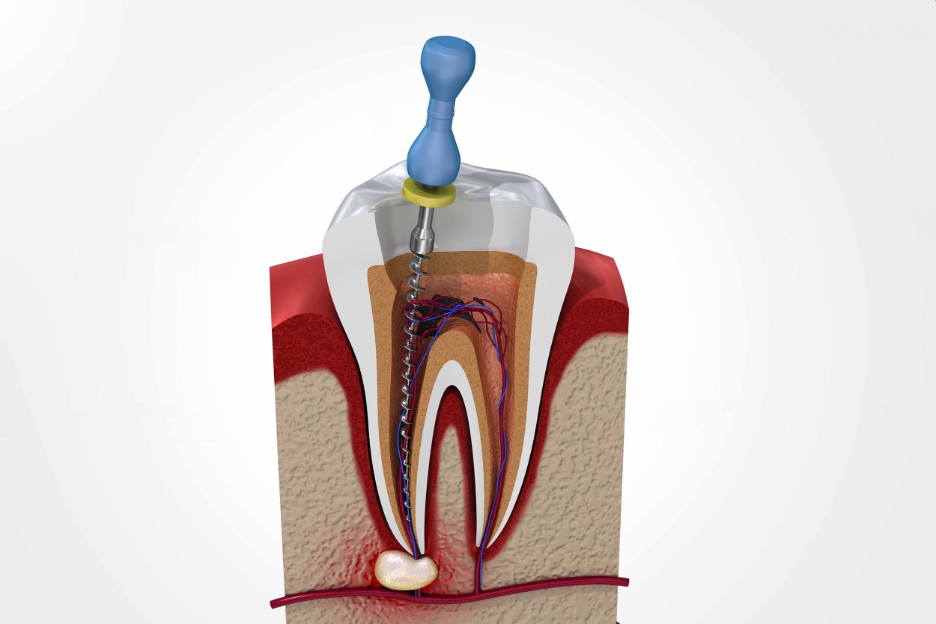

The root canal treatment aims to remove all infection, and then fill the canal system with inert dental material to prevent bacteria from re-colonizing inside the tooth. Root canal treatment (RCT), is a skilled and time-consuming procedure. Most courses of treatment will involve two visits or more to your dentist. Sometimes prophylaxis antibiotics are prescribed that help to reduce the infection and then RCT is performed in the following steps:

● In the next step, the tooth is opened by cutting burs by using a handpiece to access the canals with endo files, and pus is drained in case of an abscess or infection.

● The infected pulp is removed from the canals, which makes the tooth dead and pain free.

● The canals inside the root are cleaned and shaped with tiny instruments called files in single and multiple visits, followed by the root canals are sealed with gutta-percha points or root canal paste in baby teeth. This process is called obturation.

● After the filling of roots, the tooth is filled with a choice of filling material, and the lost structure is built with the help of fiber post if needed.

● Lastly, the root canal-treated tooth is covered with a crown (ceramic, zirconia, porcelain fused to metal, metal) to prevent it from fracture under chewing forces can cause reinfection.